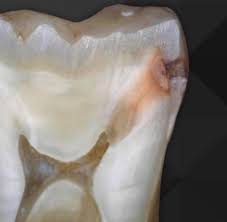

Your Enamel Is Under Constant Attack

Every beverage you consume creates an acid challenge in your mouth. A peer-reviewed study in the Journal of the American Dental Association tested 379 beverages available in the U.S. and found that 93% had a pH below 4.0 — well below the critical enamel dissolution threshold (Reddy et al., JADA, 2016; PMID: 26653863). A PRISMA-compliant systematic review of 19 studies confirmed that habitual consumption of carbonated acidic beverages causes structural disintegration and reduction of enamel's physical and mechanical properties (Cataldo et al., Nutrients, 2023; PMID: 37049624).

The demineralization process dissolves hydroxyapatite crystals — the mineral backbone of enamel — releasing calcium and phosphate ions. Once enamel is lost, it does not regenerate. This is not cosmetic damage. It is irreversible structural loss.